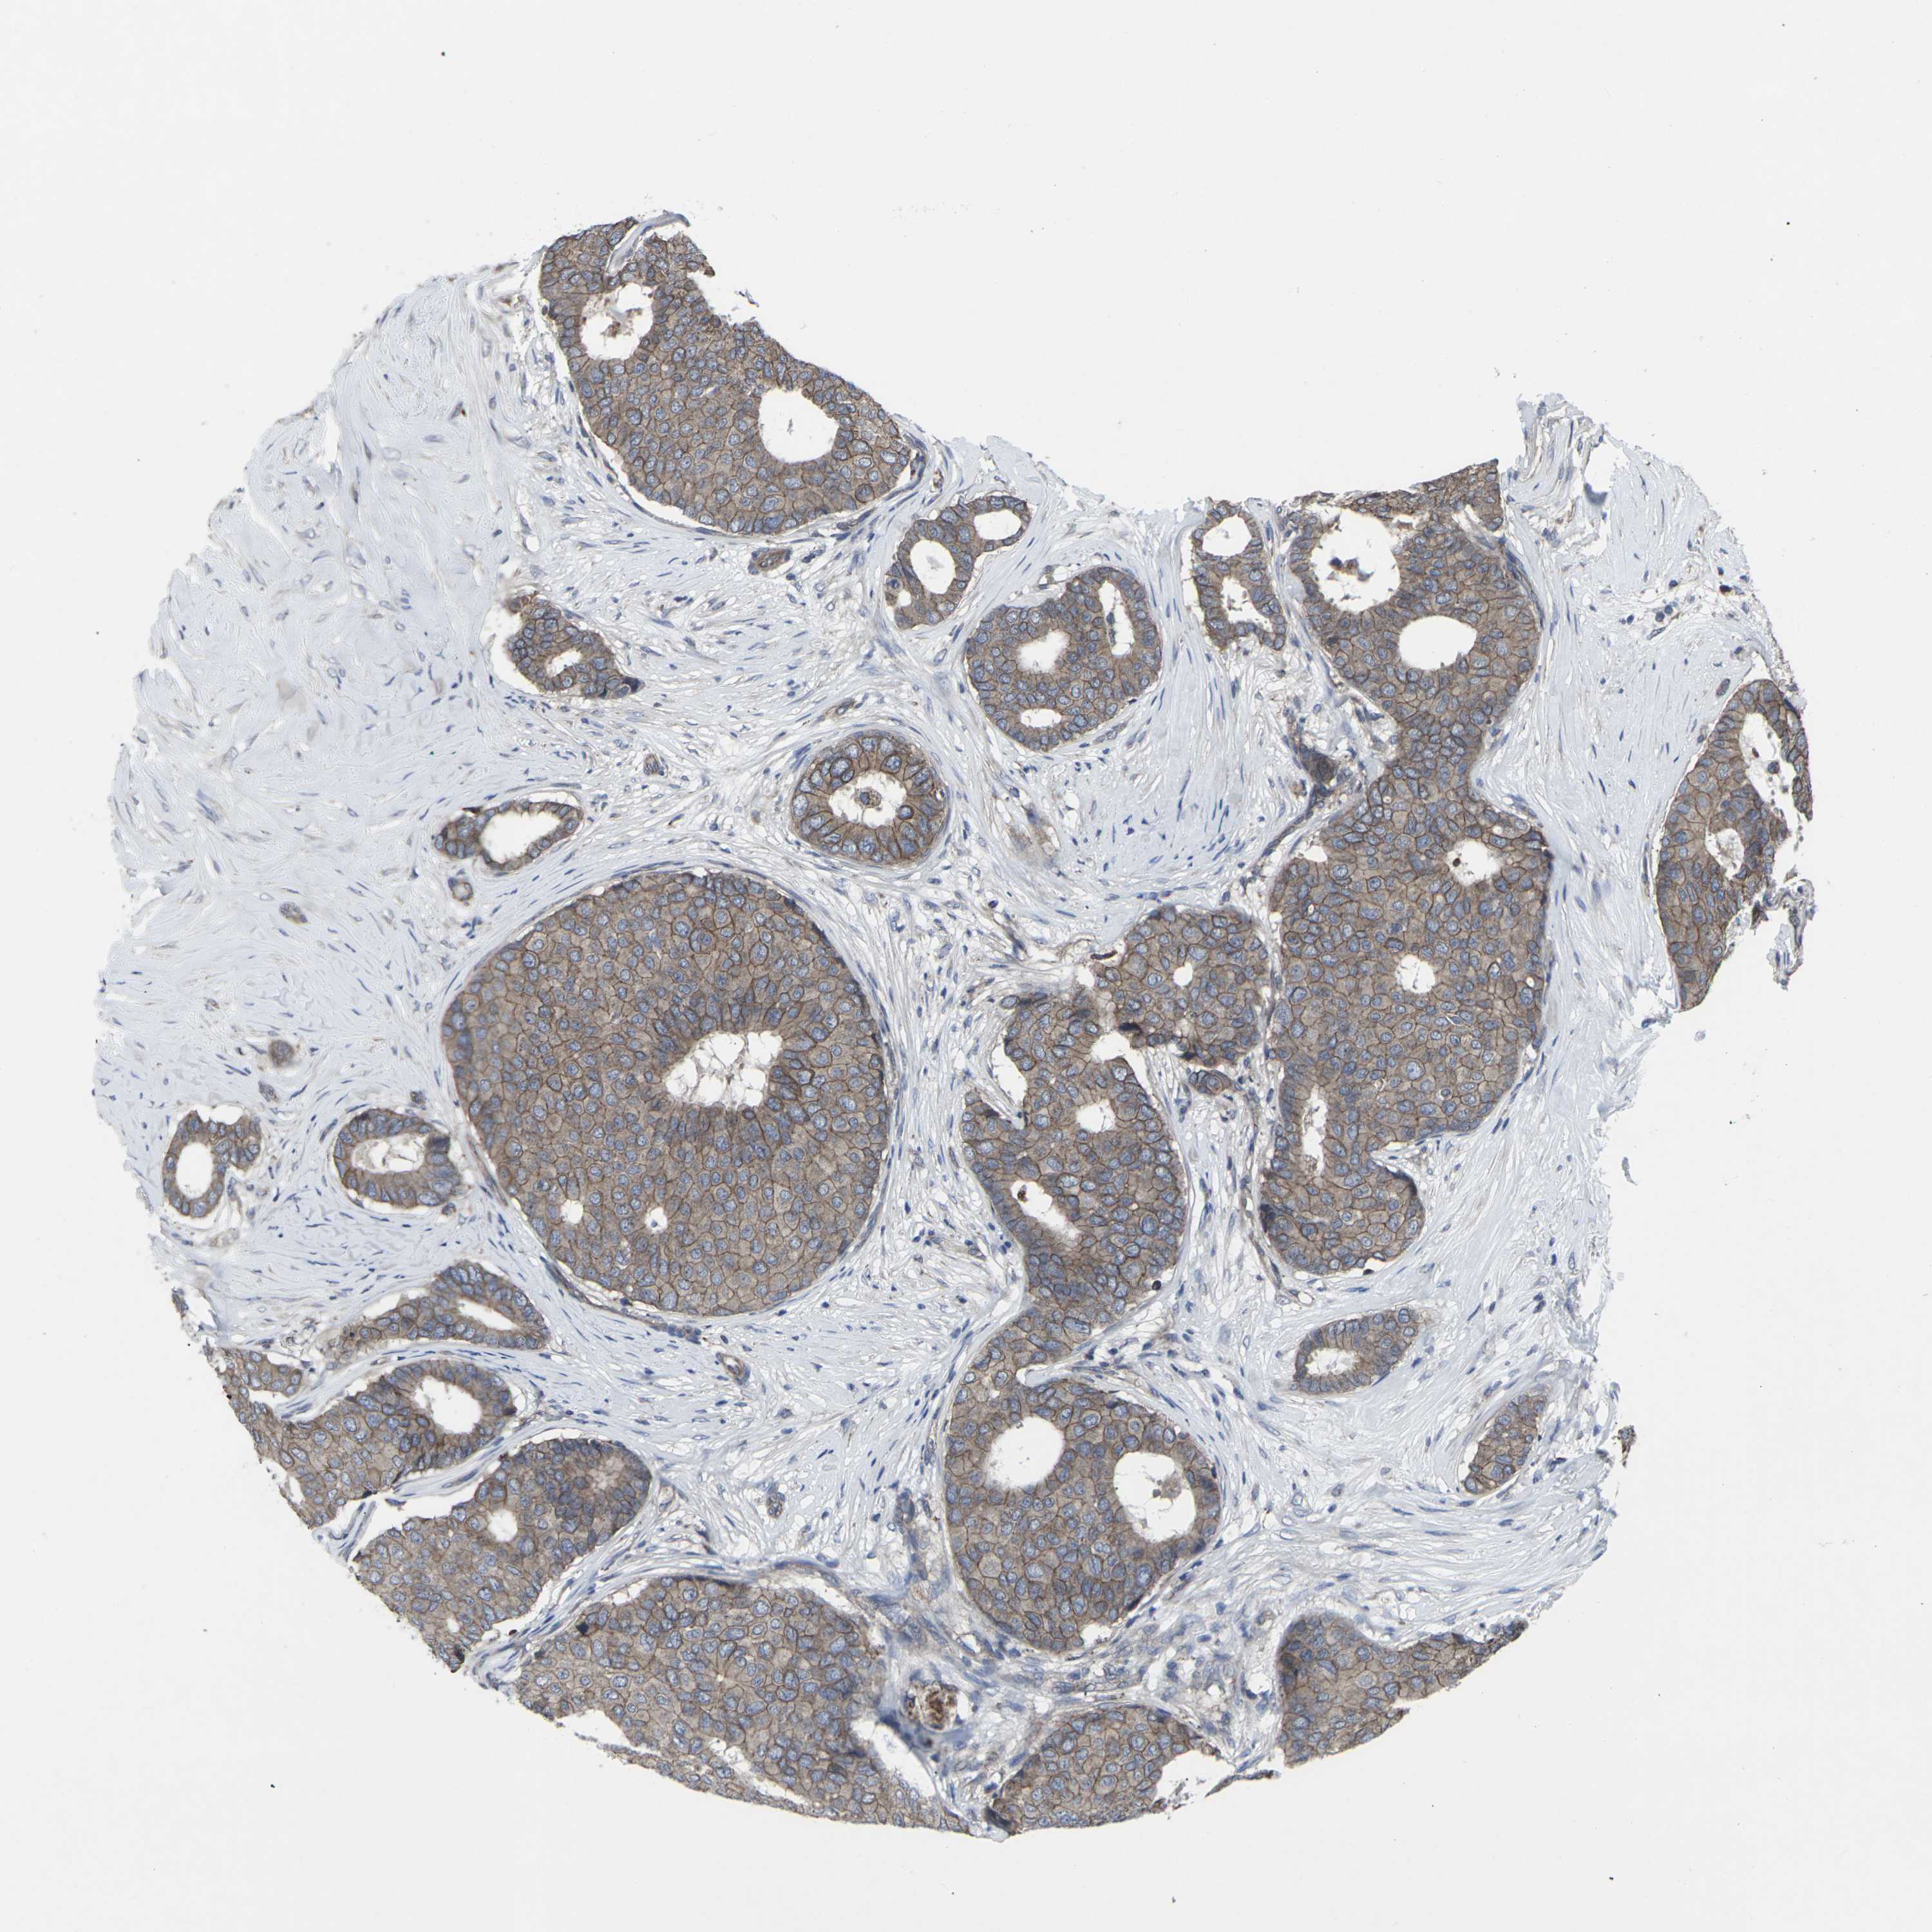

BRCA TCGA BRCA VALIDATION PROTEIN EXPRESSION

Breast cancer

Human cancer